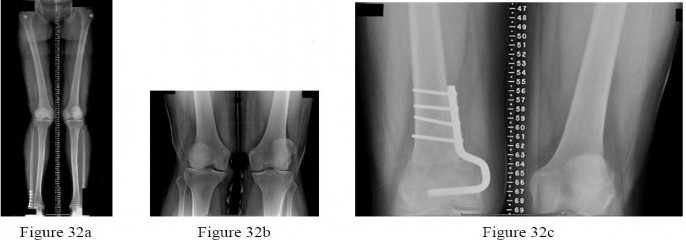

are the radiographs of a 25-year-old woman whose pain has progressed during the last several years to pain with any activity and pain at night. What is the most appropriate treatment?

---

This patient is a good candidate for a joint-preserving procedure. Her symptoms and radiographic findings reveal valgus malalignment of the knee with narrowing of the lateral joint space. The alignment can be corrected with a varus-producing distal osteotomy as shown in Figure 32c.

Most patients do not proceed to knee arthroplasty for at least 10 years after this procedure. Osteotomy is preferred over partial or total knee arthroplasty because of the patient’s young age. Varus proximal tibial osteotomy would result in joint line obliquity. PREFERRED RESPONSE: 2